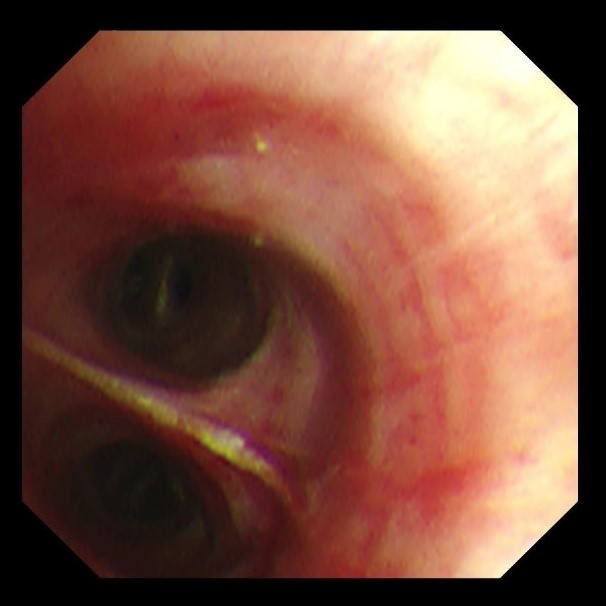

(远端支气管治疗后)

此例患者复杂异物的成功救治,不仅突破传统处理难点,还应用了三大技术创新:1.优先保护气道:使用8.5号气管插管保障通气,同时为支气管镜操作提供充足空间;2.分次清除策略:首次清除大块异物以缓解严重梗阻,二次利用超细镜实现远端精细化清理;3.冷冻技术辅助:针对细支气管的微小泥沙异物,冷冻技术有效避免传统吸引操作导致的黏膜损伤。